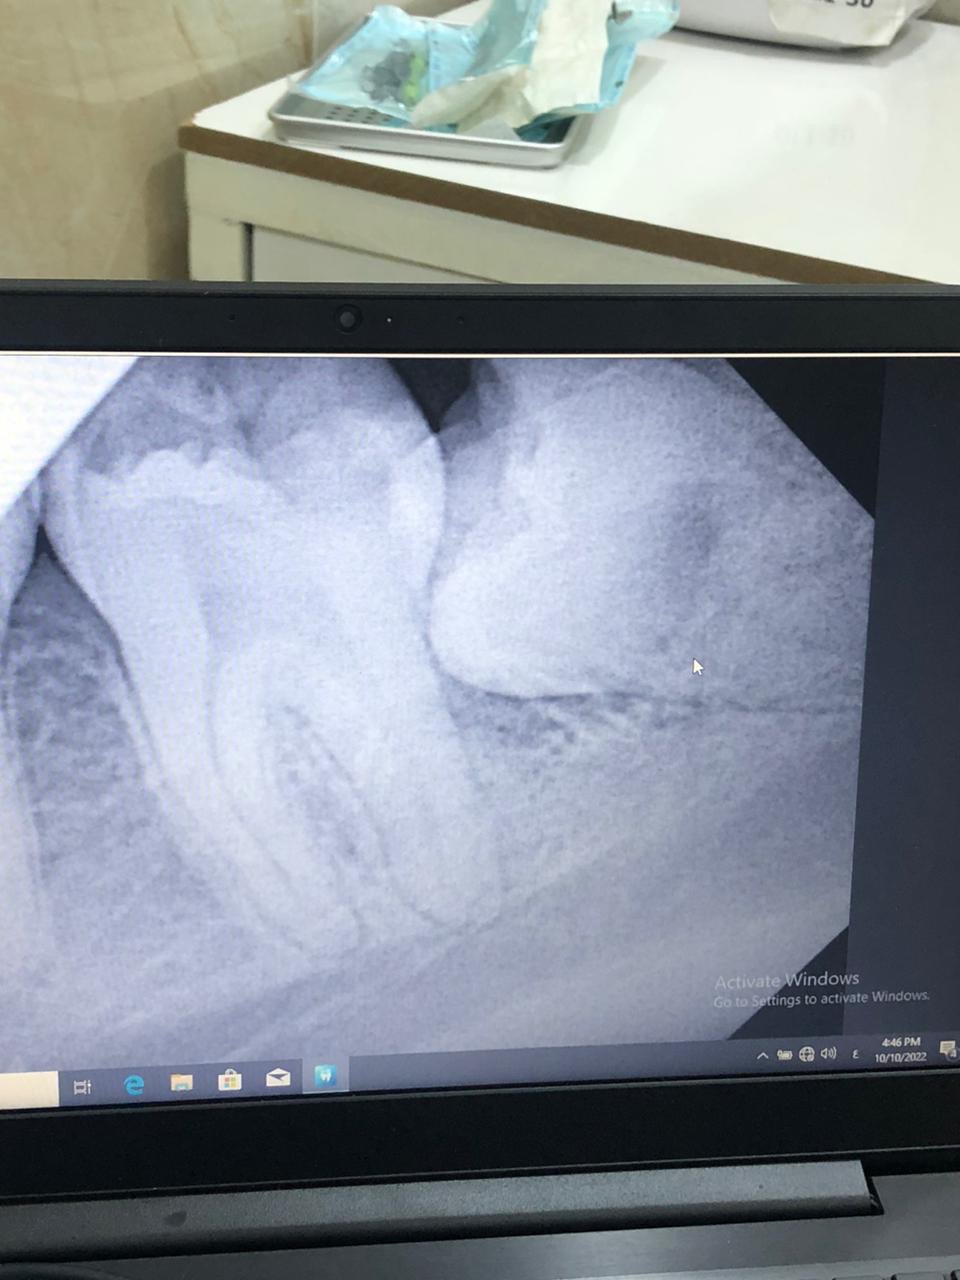

Performing a group of surgical extractions in the dental surgery clinic by the fourth and fifth stage students and under the supervision of the specialist Dr. Mohammad Ali Shaalan, Dr. Ali Adel and Dr. Hassan Khaled Hassan